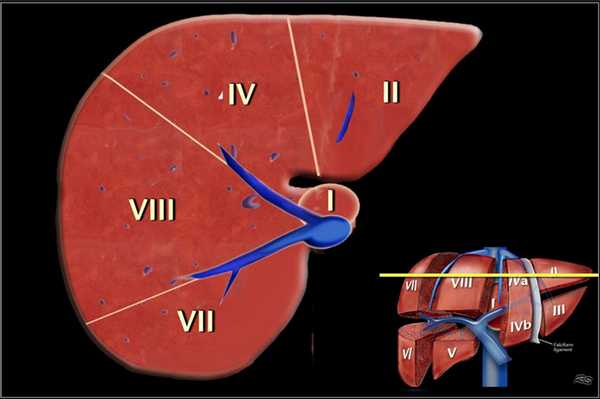

Классификации Couinaud.

По классификации Couinaud печень делится на восемь независимых сегментов. Каждый сегмент имеет свой собственный сосудистых приток, отток и желчный проток. В центре каждого сегмента есть ветви воротной вены, печеночной артерии и желчного протока. На периферии каждого сегмента вены, собирающиеся в печеночную вену.

- Правая печеночная вена делит правую долю печени на передний и задний сегмент.

- Средняя печеночная вена делит печень на правую и левую доли. Эта плоскость проходит от нижней полой вены до ямки желчного пузыря.

- Серповидный связка отделяет левую долю с медиальной стороны — сегмент IV и с латеральной сторон — сегмент, II и III.

- Воротная вена делит печень на верхние и нижние сегменты. Левая и правая воротная вена делится на верхние и нижние ветви, устремляясь в центр каждого сегмента. Изображение представлено ниже.

На рисунке изображено печеночные сегменты, фронтальный вид.

- На нормальной фронтальной проекции VI и VII сегментов не видно, поскольку они расположены более кзади.

- Правая граница печени формируется из сегментов V и VIII.

- Хотя сегмент IV является часть левой доли, он расположен правее.

Couinaud решил разделить печень в функциональном плане на левую и правую печень по проекции средней печеночной вены (линия Кэнтли).

Линия Кэнтли проходит от середины ямки желчного пузыря кпереди до нижней полой вены кзади. Изображение представлено ниже.

Нумерация сегментов.

Есть восемь сегментов печени. Сегмент IV — иногда делится на сегмент iva и ivb в соответствии Bismuth. Нумерация сегментов по часовой стрелке. Сегмент I (хвостатой доле) расположена кзади. Он не виден на фронтальной проекции. Изображение представлено ниже.